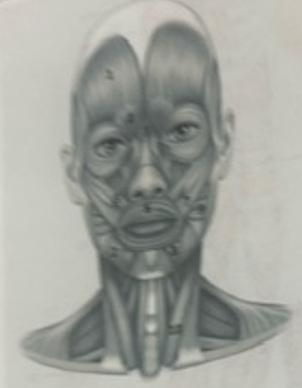

What muscle is 1?

Frontalis

What muscle is 2?

Depressor anguli oris

What muscle is 3?

Depressor labili inferioris

What muscle is 4?

Corrugator supercili

What muscle is 5?

Orbicularis oris

What muscle is 6?

Zygomaticus minor

What muscle is 7?

Zygomaticus major

What muscle is 9?

Buccinator

What muscle is 10?

Sternocleidmastoid

What muscle is 11?

Temporalis

What muscle is 12?

Masseter

What muscle is 13?

Risorius